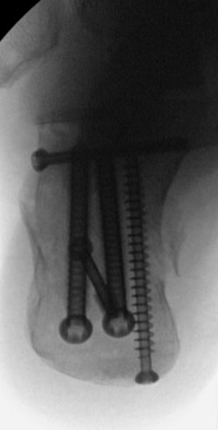

TOTAL ANKLE REPLACEMENT :: ORIF CALCANEUS :: ORIF ANKLE FRACTURE DISLOCATION :: COMPLEX BUNION AND LESSER TOE CORRECTION :: TALUS FRACTURE -1 :: TALUS FRACTURE -2 :: LISFRANC REPAIR :: COMPLEX TRIPLE ARTHRODESIS 1 :: COMPLEX TRIPLE ARTHRODESIS 2 :: MINIMALLY INVASIVE BUNION REPAIR 1 :: MINIMALLY INVASIVE BUNION REPAIR 2 :: ARTHROSCOPIC CARTILAGE REPAIR :: TENEX SPUR DEBRIDEMENT :: Haglunds Debridement and Achilles Repair